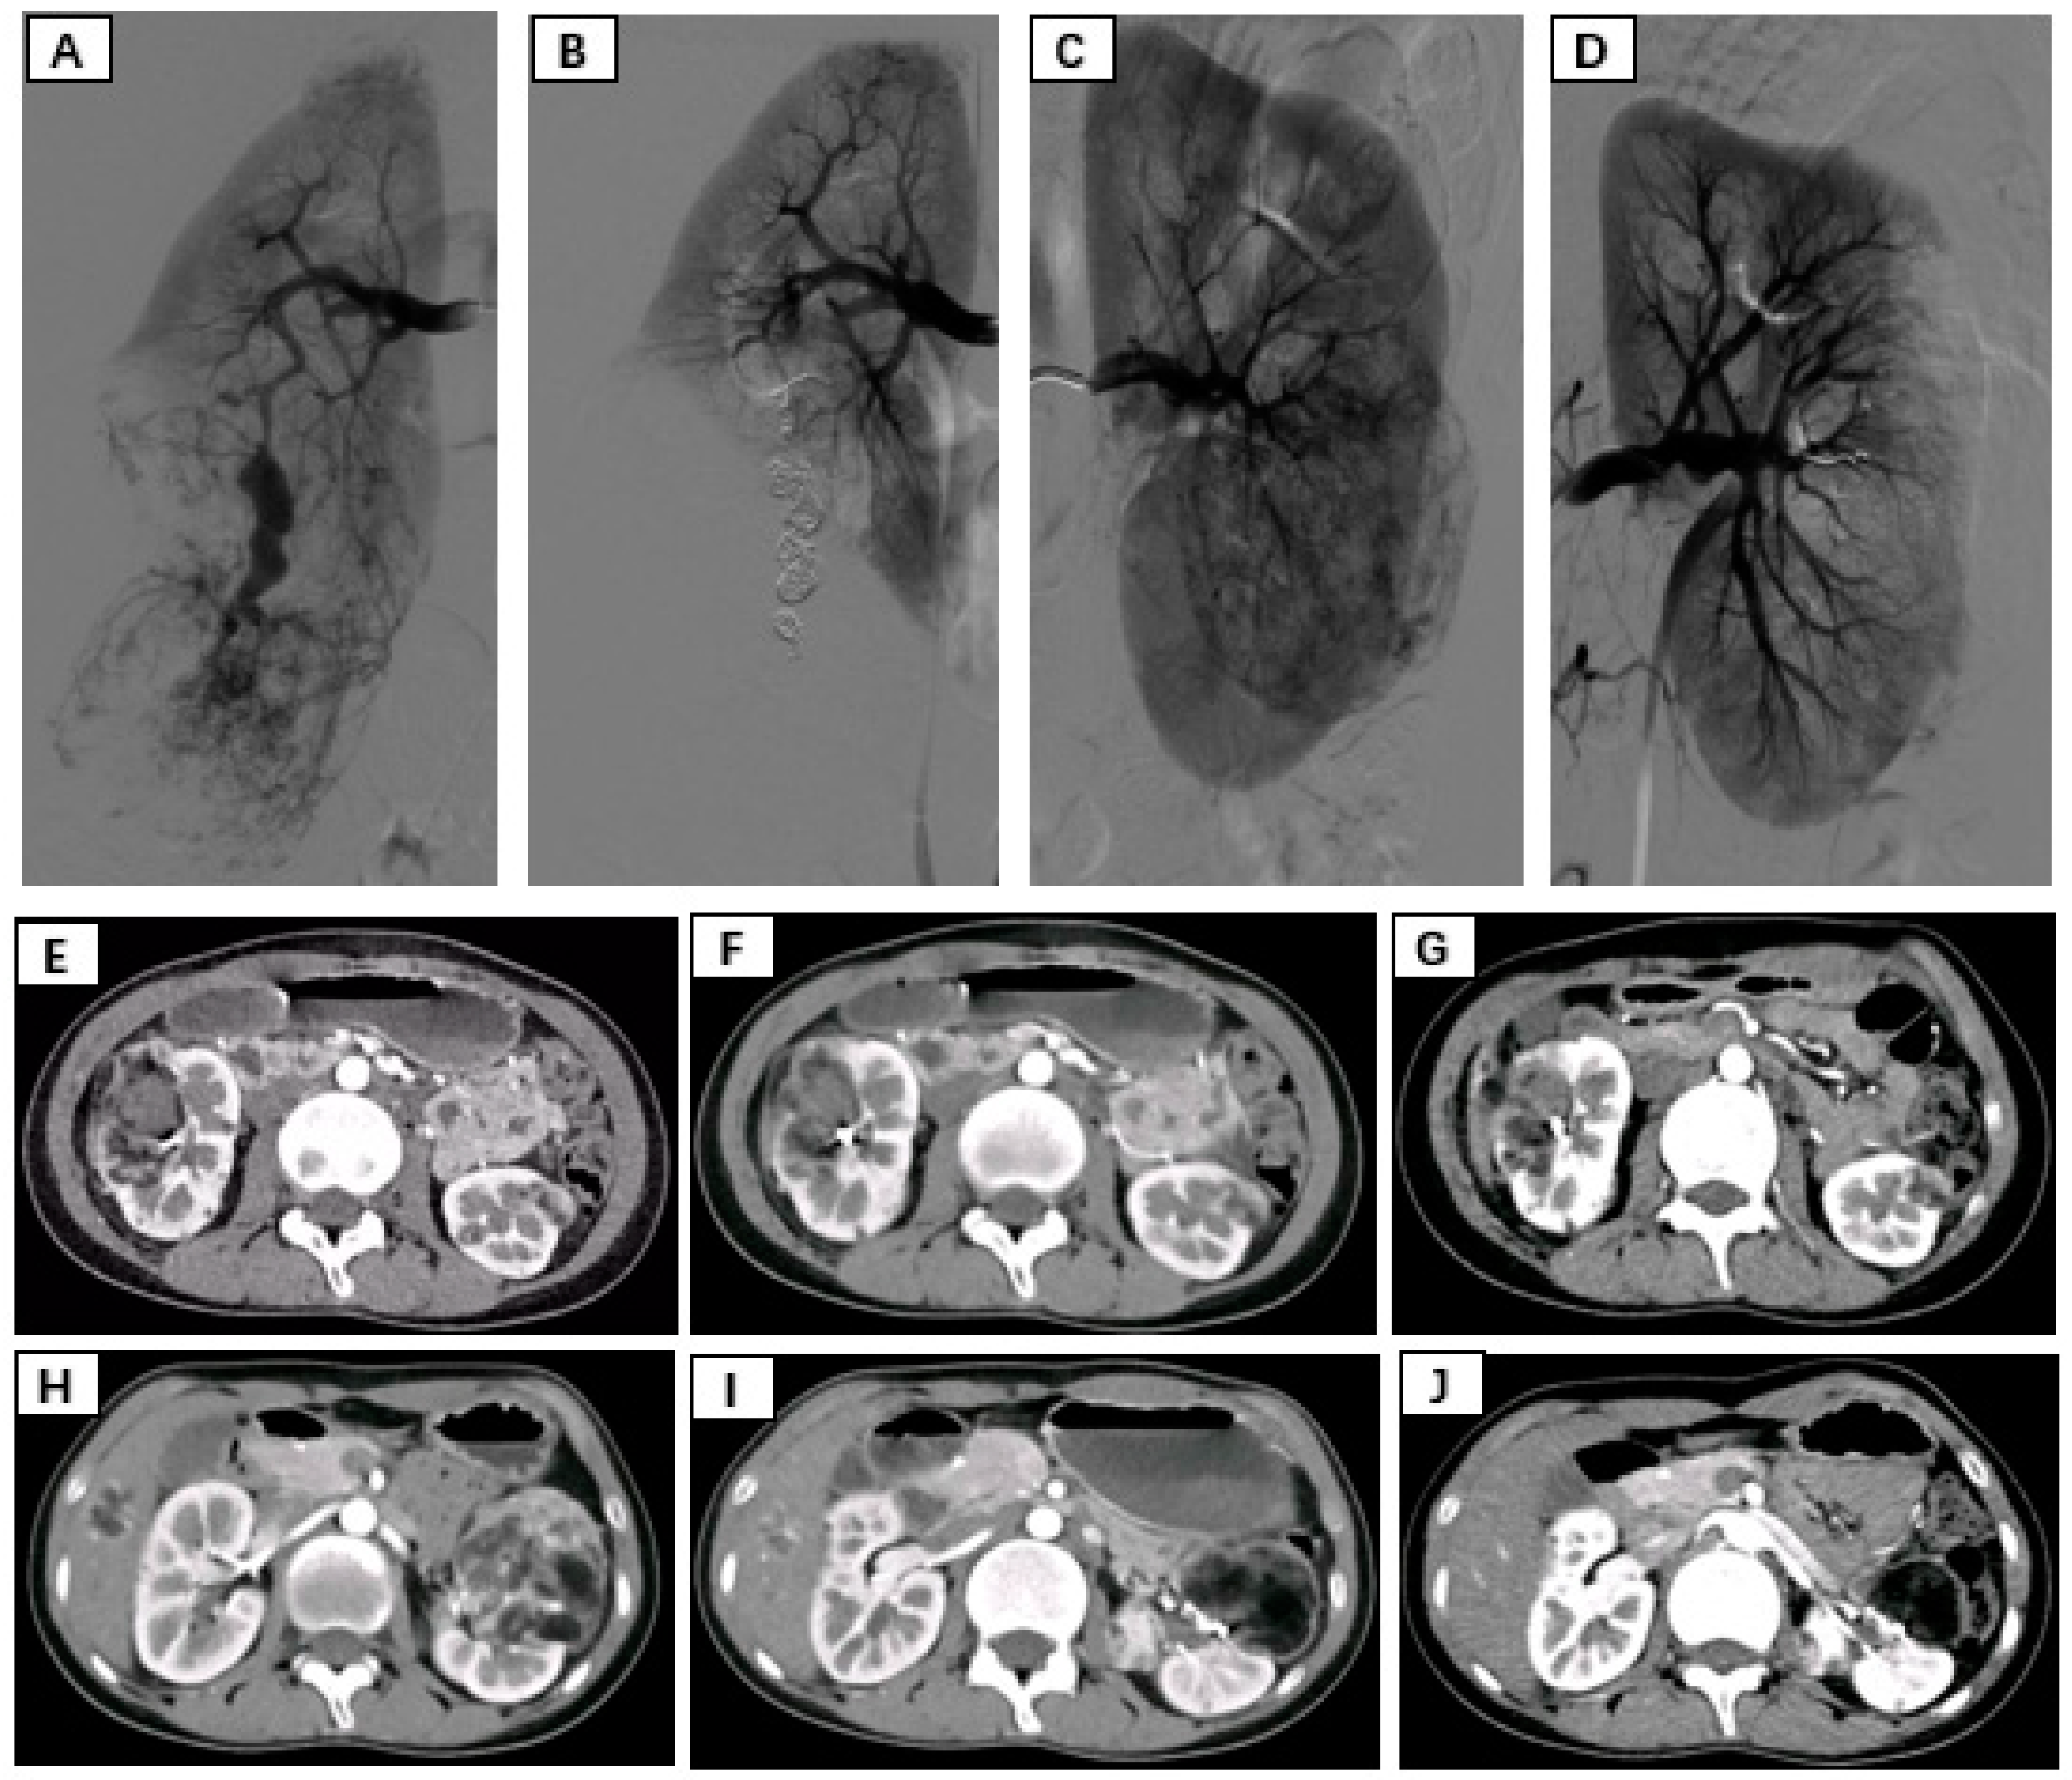

Patients were placed in the supine position and routinely disinfected and toweled. The right common femoral artery was used as the puncture point for all patients. Local anesthesia with 1% lidocaine was administered, and the modified Seldinger method was used for retrograde puncture of the right femoral artery. After successful puncture, a 6F sheath (Cordis, Hialeah, FL, USA) was inserted under the guidance of a 0.035 inch × 150 cm guidewire (Boston Scientific, Alpharetta, GA, USA), and a 5F PIG (Cordis, USA) catheter was advanced to the upper segment of the abdominal aorta. High-pressure injection angiography was performed to locate the opening of the renal artery and determine the number, morphology, and lesion location of the renal arteries, followed by selective renal arteriography. Under the guidance of a 0.035 inch × 150 cm supersmooth guidewire, a 5F C2 catheter (Cordis, USA) was advanced to the opening of the diseased side renal artery. Renal artery openings were localized using high-pressure syringe angiography to determine the number, morphology, and location of the renal arteries. Depending on the size of the target vessel diameter, microguidewires (Asahi Intecc Co., Ltd., Seto-shi, Japan) were used to guide the insertion of either a 1.98Fr or 2.6Fr coaxial microcatheter (Asahi Intecc Co., Ltd., Japan) into distal branches at levels two or three in the renal artery. High-pressure injection angiography again revealed signs such as direct bleeding from the extravasation contrast agent and tortuous enlargement with structural disorder along with vascular composition outlining tumor contours in blood supply arteries feeding into tumors. After careful assessment of the tumor’s blood supply, a suspension of polyvinyl alcohol (PVA) embolic agent (COOK, Bloomington, IN, USA) mixed with an appropriate amount of contrast agent (usually at a concentration of 30% to 40%) was prepared. Under vascular angiography and fluoroscopy, the PVA particle suspension was injected into the tumor-feeding artery through a microcatheter at an appropriate speed to avoid reflux. For patients with concomitant arterial aneurysms, embolization coils (COOK, USA) of suitable diameter and quantity were used for embolization based on the target vessel diameter. For patients without arterial aneurysms, if incomplete embolization was observed after the use of PVA particles, spring coils were used to embolize the main tumor-feeding artery. In cases where the tumor was supplied by multiple arteries, selective embolization of each branch vessel with appropriately sized PVA was performed to minimize damage to normal renal units. Subsequent DSA revealed no distal visualization or extravasation of contrast agent in the branch vessels supplying the renal tumors. The right femoral artery puncture site was closed using a vascular closure device followed by hemostatic compression and pressure bandaging. After completion of the procedure, the patient returned to the ward for bed rest with immobilization of the right lower limb for 24 h while being closely monitored for any signs of bleeding from the puncture site (Figure 1).

Figure 1.

(A,B) Immediate pre- and postembolization imaging of the right renal angiomyolipoma. (C,D) Immediate pre- and postembolization imaging of the left renal angiomyolipoma. (E–G) Rupture and hemorrhage of the right renal angiomyolipoma, followed by 3-month, 6-month, and 12-month follow-up contrast-enhanced CT showing a significant reduction in tumor size. (H–J) Pre-embolization, 3-month postembolization, and 6-month postembolization follow-up contrast-enhanced CT images of the left renal angiomyolipoma demonstrating a marked reduction in tumor size.

7. Follow-Up

The average follow-up period after surgery for both groups of patients was 22 months, and all patients received outpatient follow-up. In the SAE group, postembolization re-examination via bilateral renal CT revealed a significant reduction in tumor diameter, indicating remarkable therapeutic efficacy. During the follow-up period, neither group underwent further surgery, and there was no tumor recurrence. In the SAE group, the average tumor diameter decreased by 3.33 cm compared to that in the pre-embolization group (p < 0.05) (Table 4).